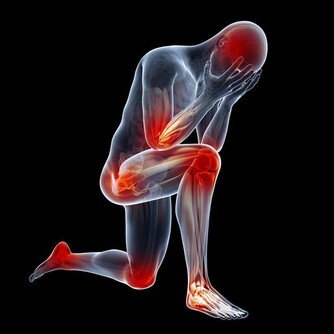

四、皮膚異常

對於出現卵巢早衰的女性來講,皮膚會發生一系列的異常改變。由於體內的雌激素大量降低,就會使得膠原蛋白減少,這種成分一旦減少,皮膚的彈性就會快速下降,從而使皮膚變得非常粗糙、鬆弛。

而且還會長出很多的皺紋,並且會變得特別敏感,很容易出現過敏現象。另外,女性全身的皮膚都會非常乾燥,很容易出現脫屑現象。